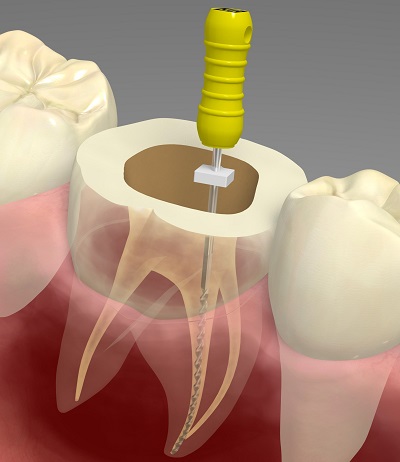

根管治療

根管治療とは、虫歯が神経にまで到達したときに神経を除去する、あるいは一度根管治療された歯において、何らかの理由で感染した根管を再治療することです。

根管治療とは、虫歯が神経にまで到達したときに神経を除去する、あるいは一度根管治療された歯において、何らかの理由で感染した根管を再治療することです。

虫歯が神経まで到達すると、冷水痛、温水痛、自発痛などの痛みを伴います。そのため、神経を除去し、根管内を清掃、殺菌した上で薬剤を充填し、歯の保存を行います。

根管治療後には、被せ物を装着し、その審美性と機能性を回復させます。

CTによる精密な診断

根管は、非常に複雑な形をしています。手技のみに頼っていては確実な治療ができません。当院では、CT検査で根管の状態を3次元的に把握し、診断に役立てるとともに、正確な治療につなげています。

根管は、非常に複雑な形をしています。手技のみに頼っていては確実な治療ができません。当院では、CT検査で根管の状態を3次元的に把握し、診断に役立てるとともに、正確な治療につなげています。

また、複雑な根形態の場合のCT撮影は保険適用となりますので、随時お伝え致します。

ラバーダムを使用し、

細菌感染を防止

根管治療では、根管を徹底的に清掃・殺菌した上で、薬剤を充填しなければなりません。少しでも唾液が入ってしまうと、唾液中の細菌によって後から感染を起こしてしまうためです。

根管治療では、根管を徹底的に清掃・殺菌した上で、薬剤を充填しなければなりません。少しでも唾液が入ってしまうと、唾液中の細菌によって後から感染を起こしてしまうためです。

当院では、治療をする歯だけを露出させるラバー製のシート「ラバーダム」を使って、根管治療中の細菌の感染を防いでいます。精密な根管治療には、欠かせないひと手間です。